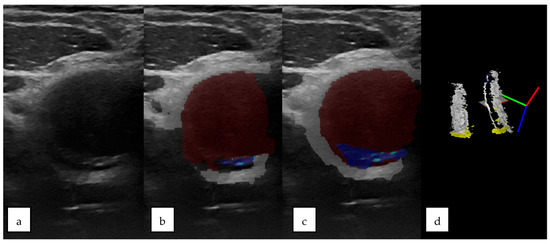

3.1. 2D Automatic Segmentation

3.1.1. Automatic Segmentation Results Compared with the Gold Standard (Operator’s Segmentation)